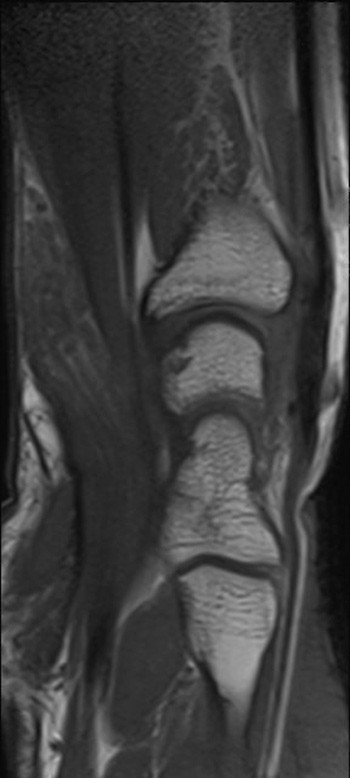

A previously healthy teenage girl was referred to the department of hand surgery with a lump on the flexor side of the left wrist. The lump had been discovered by the girl’s mother around seven years earlier and had gradually become increasingly painful. The patient described hypersensitivity to touch and numbness in the thumb, index, middle and ring fingers. Percussion over the tumour produced radiating pain and increased numbness in the same fingers. MRI showed an enlarged median nerve with a cable-like appearance due to fibrous thickening of the peri- and endoneurium and increased fat separating the roughly 15 nerve fibres (images online). The tumour was approximately 10 cm in size. A lipofibromatous hamartoma was diagnosed on the basis of the MRI findings, which are pathognomonic for the condition (1).

Surgical exploration of the tumour was performed, along with carpal tunnel decompression. At its widest point the tumour (see image) had a diameter three times the size of a normal nerve. At check-ups two and six months later, the patient was still experiencing the same pain as prior to surgery, but sensation in the fingers had improved. Neurography after two months showed moderate axonal and demyelinating sensorimotor neuropathy of the median nerve at the level of the wrist and carpus, suggesting compression neuropathy. EMG examination revealed sparse denervation activity and findings consistent with reinnervation. There were no previous examinations with which to compare the results.